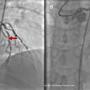

Early Recognition and Intervention of De Winter Syndrome: A Case Report